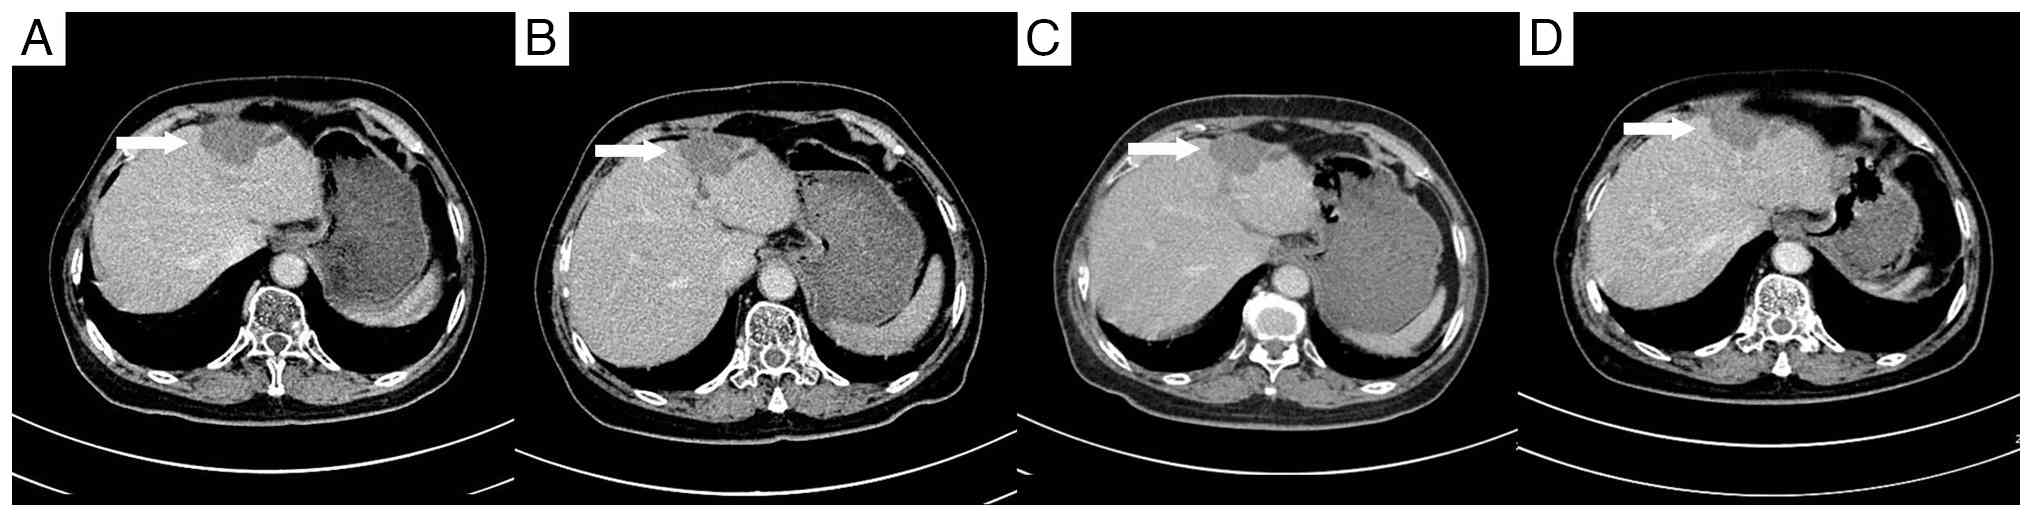

Enhanced computed tomography scans 3

months after surgery. (A) A 14×11-mm lesion beneath the liver

capsule in the right lobe (arrow). (B) An 8×7-mm lesion adjacent to

the right portal vein (arrow). (C) A 17×14-mm lesion at the apex of

the right lobe (arrow). (D) A 15×15-mm lesion in the left lobe

(arrow).

Figure 2.

Enhanced computed tomography scans 3 months after surgery. (A) A 14×11-mm lesion beneath the liver capsule in the right lobe (arrow). (B) An 8×7-mm lesion adjacent to the right portal vein (arrow). (C) A 17×14-mm lesion at the apex of the right lobe (arrow). (D) A 15×15-mm lesion in the left lobe (arrow).

As a standard approach for multiple small lesions, systemic chemotherapy was initiated 3 months after surgery, using the FOLFOX regimen (100 mg oxaliplatin by intravenous infusion on day 1; 200 mg calcium folinate by intravenous infusion on days 1–2; 500 mg fluorouracil by intravenous bolus on day 1, followed by 1,500 mg via continuous intravenous infusion over 44 h). However, the treatment was discontinued due to poor patient tolerance. A multidisciplinary consultation then recommended the use of RFA. However, the pre-procedural assessment identified the following notable challenges for RFA: The lesion beneath the liver capsule in the right lobe of the liver was relatively superficial, which could potentially lead to incomplete coverage by the radiofrequency probe and impact treatment efficacy; the lesion adjacent to the right portal vein posed a heightened risk for RFA due to its proximity to major blood vessels; and the lesion at the apex of the right lobe was too deep for adequate radiofrequency coverage.